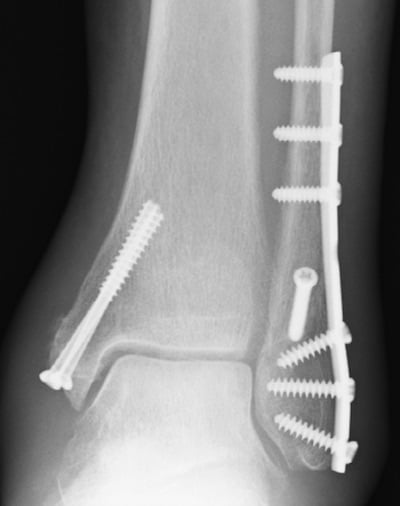

Το χειρουργείο γίνεται συνήθως με γενική +/- περιοχική αναισθησία και περιλαμβάνει τοποθέτηση εμφυτευμάτων, όπως πλάκες, βίδες, ήλους, κλπ. Ο ασθενής παραμένει σε νάρθηκα για 2 εβδομάδες, μέχρι την πρώτη μετεγχειρητική επίσκεψη, όπου και γίνεται έλεγχος του τραύματος και τυχόν αφαίρεση ραμμάτων. Το άκρο τοποθετείται σε ειδική μπότα βάδισης. Μπορεί να χρειαστείτε πατερίτσες για κάποιο διάστημα. Ο ιατρός και ο φυσικοθεραπευτής θα δημιουργήσουν ένα εξατομικευμένο πρόγραμμα αποκατάστασης για την περίπτωσή σας. Σε ορισμένες περιπτώσεις, είναι προτιμότερο το χειρουργείο να πραγματοποιείται όψιμα, αφού υποχωρήσει το έντονο οίδημα της περιοχής. Σε εξαιρετικές περιπτώσεις, το χειρουργείο γίνεται σε 2 στάδια, με αρχική τοποθέτηση εξωτερικής οστεοσύνθεσης και στη συνέχεια τροποποίηση σε εσωτερική οστεοσύνθεση.